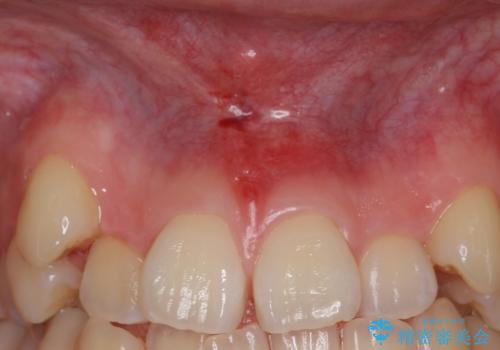

- 上顎前歯の隙間と出っ歯、八重歯が気になるため矯正をしたいといらっしゃった方の症例です。

上顎前歯の隙間と出っ歯の一因は上唇小帯と呼ばれる上唇と歯茎を結ぶ線維性の付着によるものであり、矯正を行っても後戻りのリスクが高いことから、矯正前に上唇小帯の切除を行いました。

上唇小帯とは上唇と歯茎を結ぶ線維性の付着のことです。上唇小帯の付着位置が前歯に近いと今回のケースのように正中離開(前歯の隙間)の原因となります。

- 外科手術のため、術後に出血、痛みや腫れ、違和感を伴います